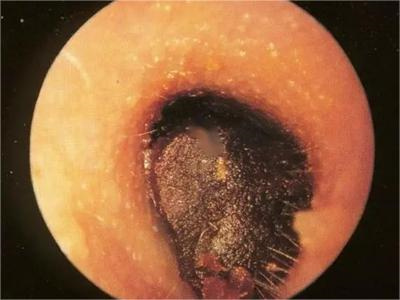

外耳道耵聍栓塞耳内有包块发亮图

外耳道耵聍栓塞患者外耳道内部有黏性分泌物不断排出,堆积后形成褐色硬块,表面有黏液包裹,光滑发亮,难以自行排出,需要通过器械协助排出。